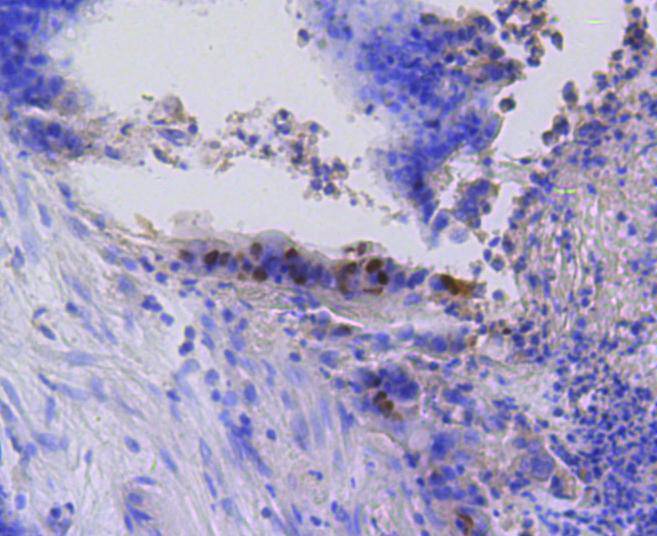

Immunohistochemical analysis of paraffin-embedded mouse spleen tissue using anti-Phospho-Rb(S807) antibody. Counter stained with hematoxylin.

Immunohistochemical analysis of paraffin-embedded human tonsil tissue using anti-Phospho-Rb(S807) antibody. Counter stained with hematoxylin.

Immunohistochemical analysis of paraffin-embedded human colon cancer tissue using anti-Phospho-Rb(S807) antibody. Counter stained with hematoxylin.

Immunohistochemical analysis of paraffin-embedded human spleen tissue using anti-Phospho-Rb(S807) antibody. Counter stained with hematoxylin.

Immunohistochemical analysis of paraffin-embedded human breast carcinoma tissue using anti-Phospho-Rb(S807) antibody. Counter stained with hematoxylin.

Immunohistochemical analysis of paraffin-embedded mouse colon tissue using anti-Phospho-Rb(S807) antibody. Counter stained with hematoxylin.